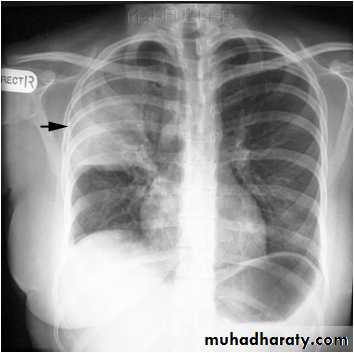

Right upper lobe consolidation

RUL consolidation will be seen as an increased opacity within the right upper lobe. Opacity may be sharply bordered by the horizontal fissureSome loss of outline of the upper right heart border may be apparent

Radiological sign in chest radiograph

Dense opacity seen above the horizontal fissure.

Air-bronchogram line

The lower border of the consolidation is sharply delinated by the horizontal fissure suggesting it lies in the anterior segment of the RUL

RT UL Consolidation